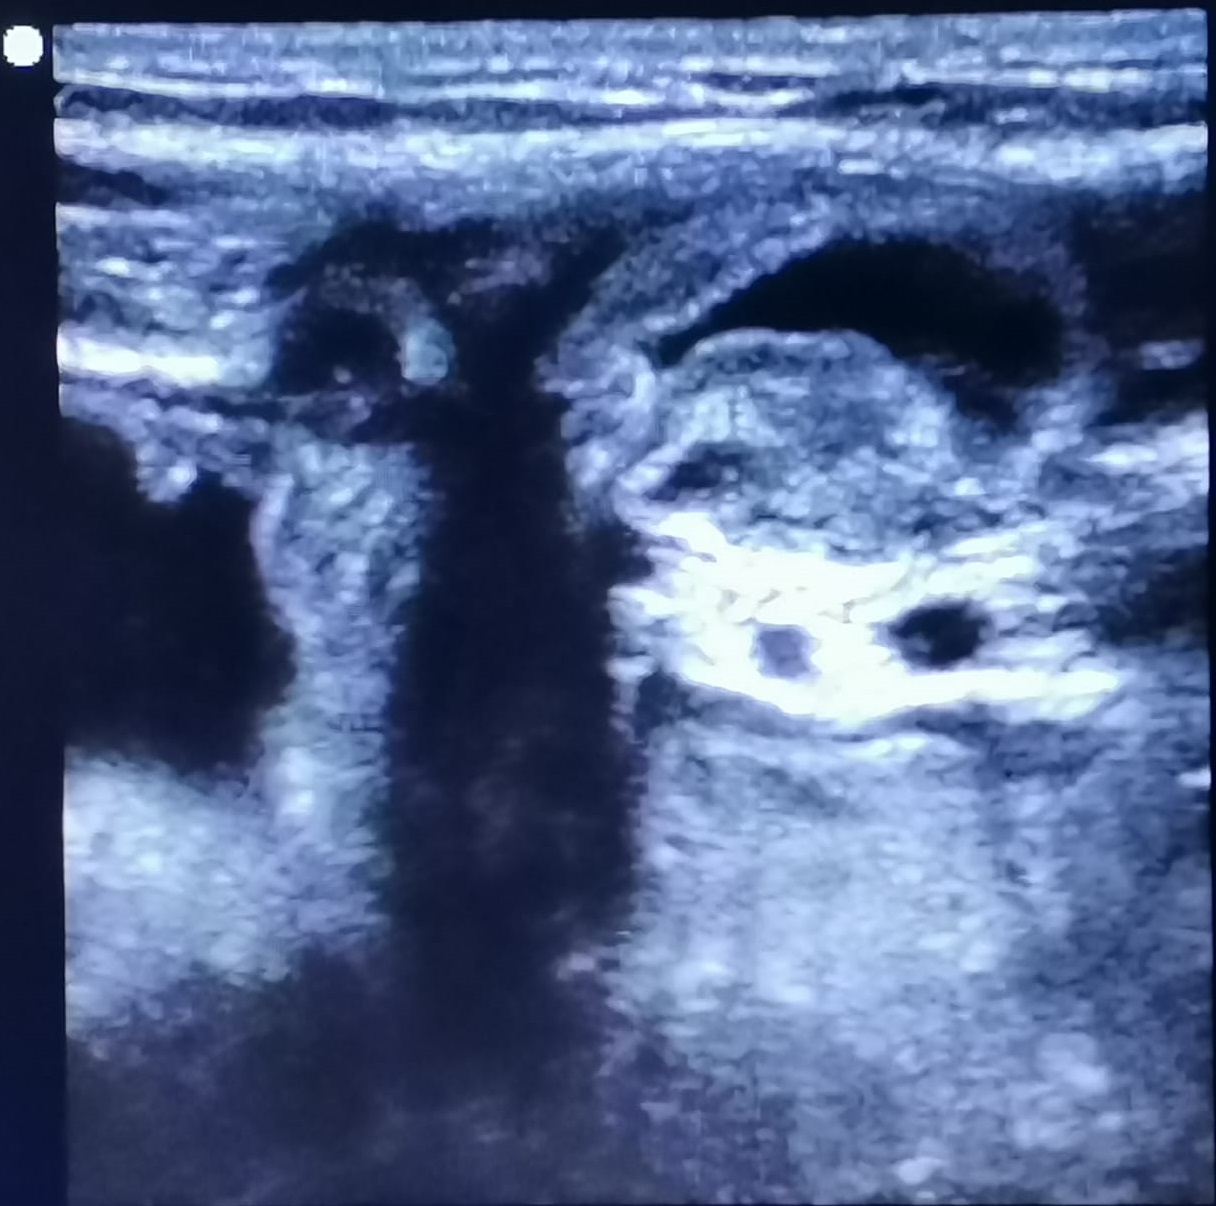

Ecografía a pie de cama: protusión de contenido hipoecogénico a través de agujero herniario, que aumenta su diámetro con maniobra de Valsalva y que no se reduce por completo; compatible con hernia inguinocrural no reductible.